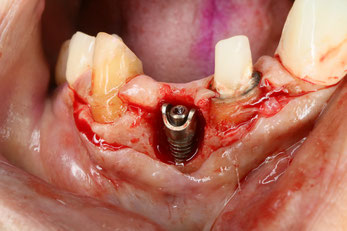

インプラントを除去した時の写真。インプラントの炎症のためにインプラント周囲に合った骨がなくなってしまっています。炎症の原因になるインプラントを除去して、骨を作ります。